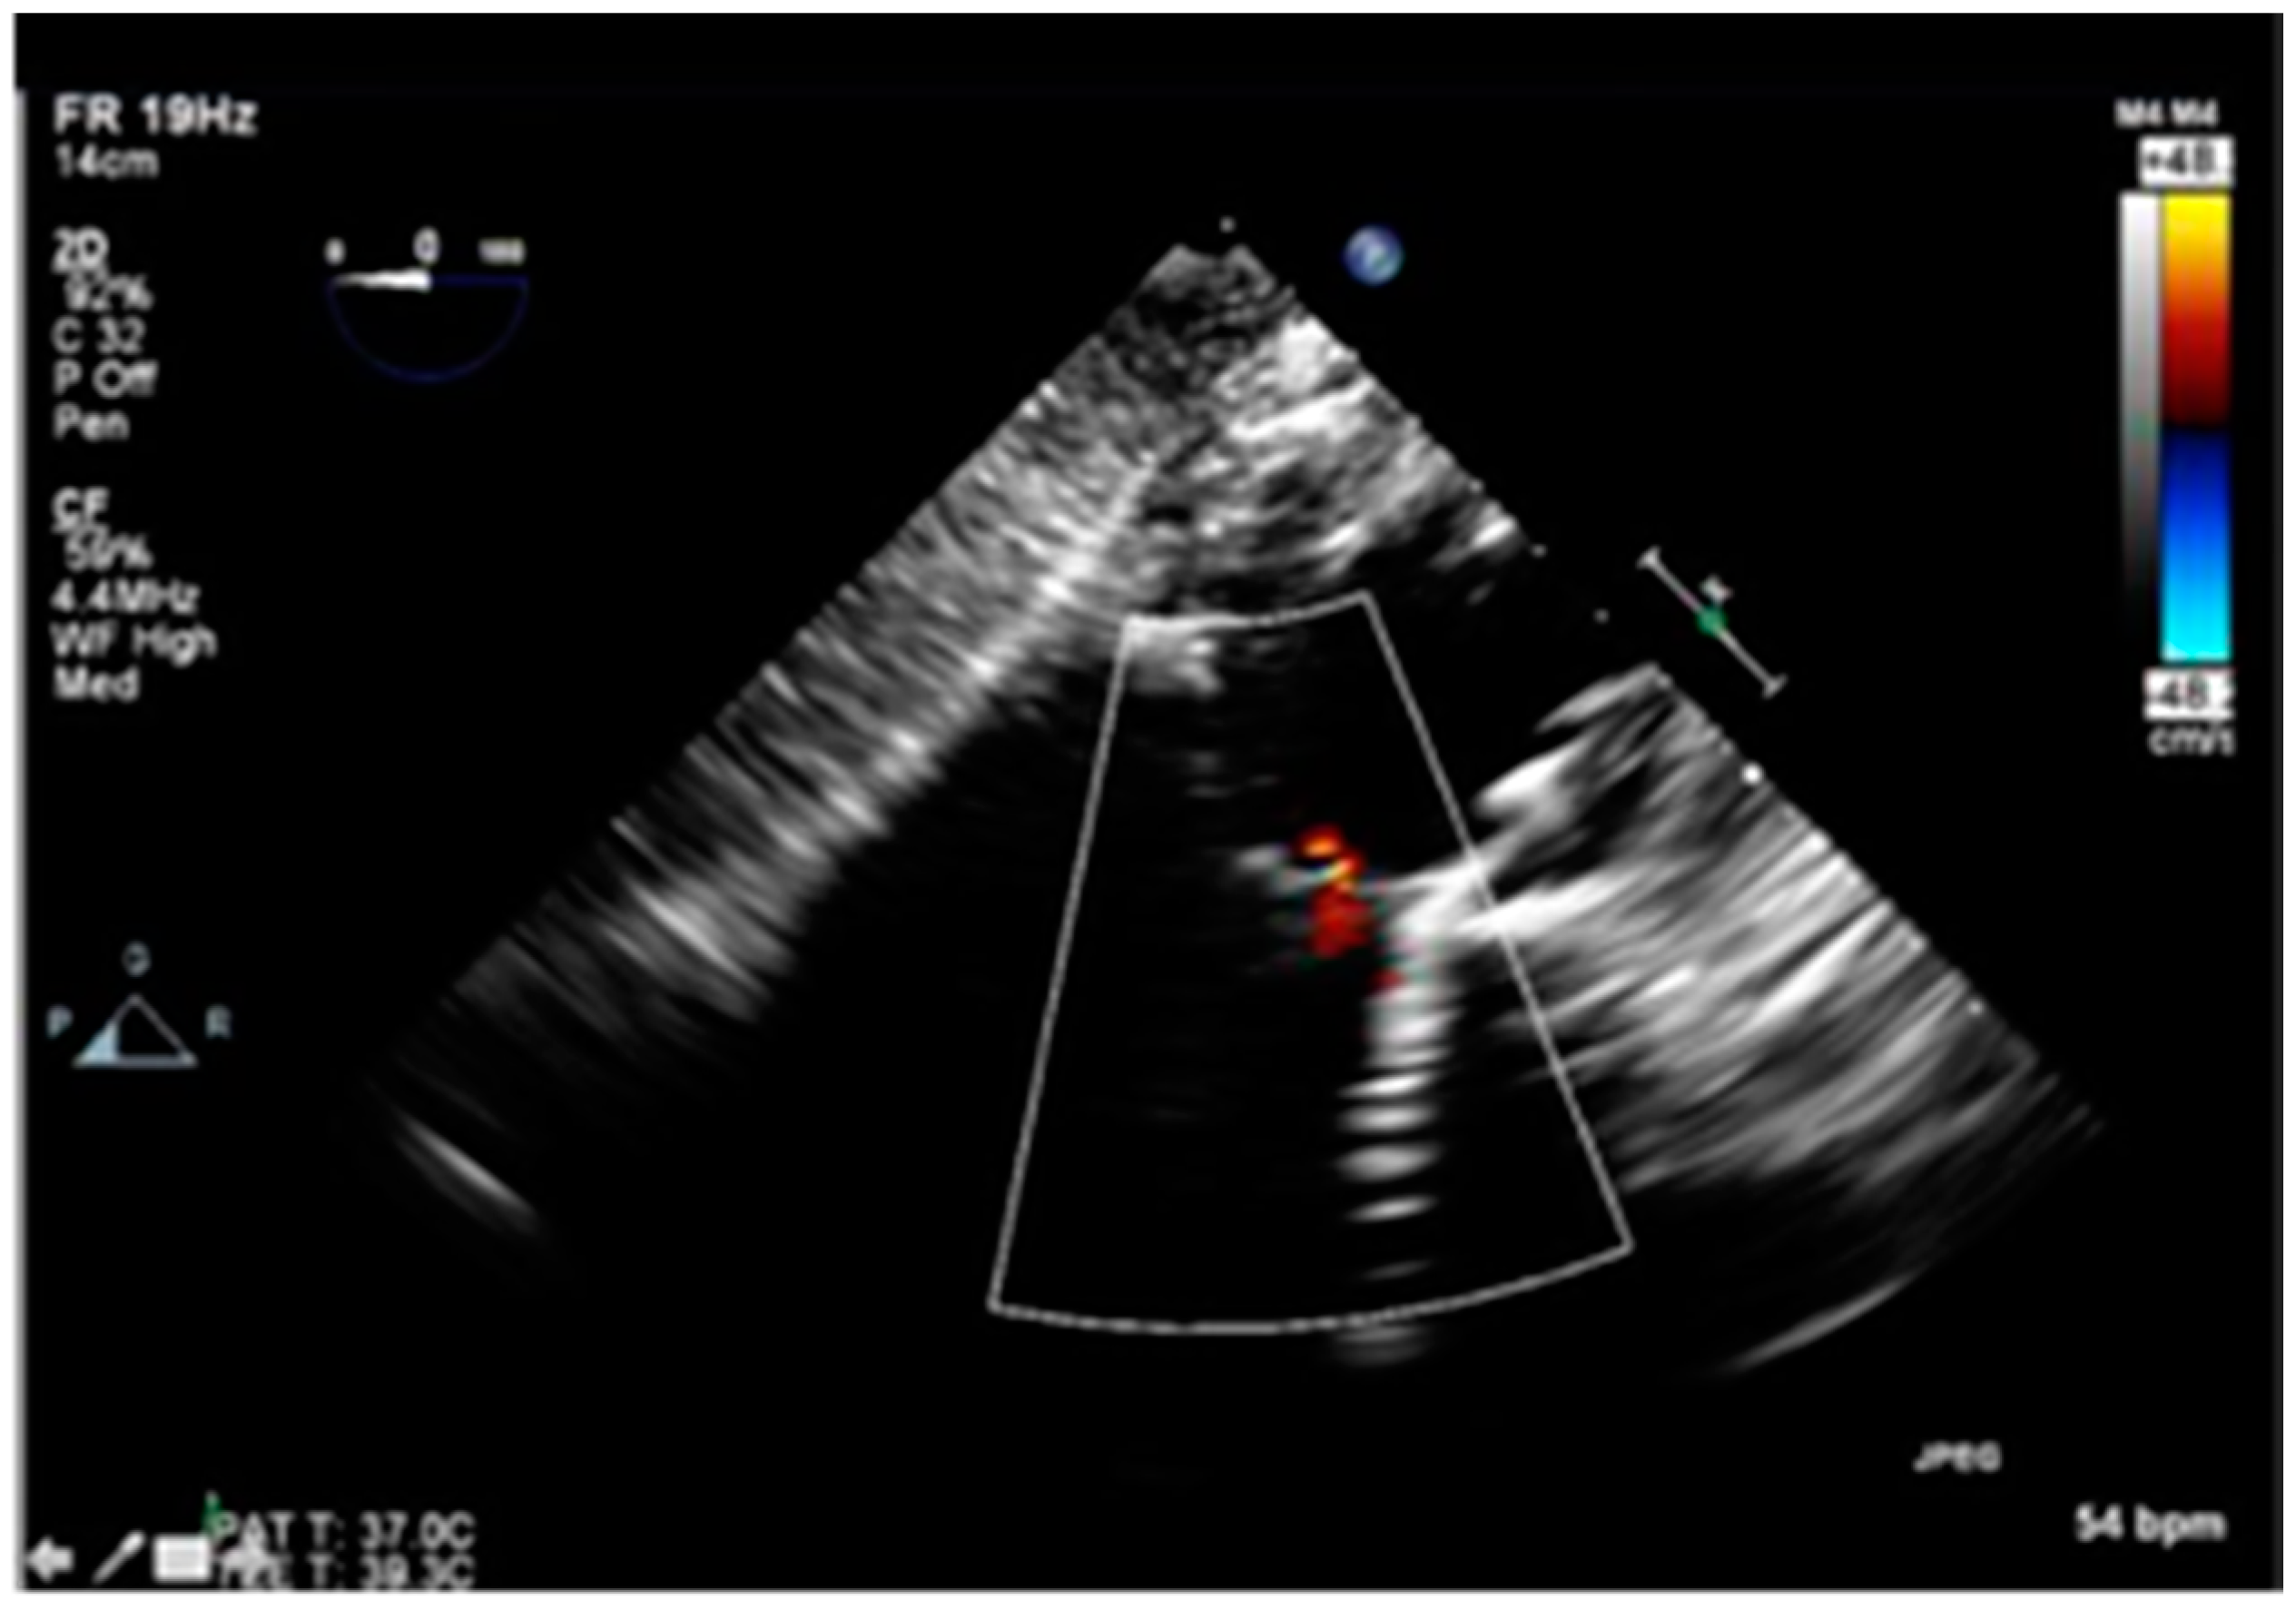

Post valvuloplasty, the patient developed significant acute aortic regurgitation with hemodynamic instability as shown in Figure 3.

Figure 3.

Intraoperative Trans-esophageal echocardiogram showing severe aortic regurgitation.